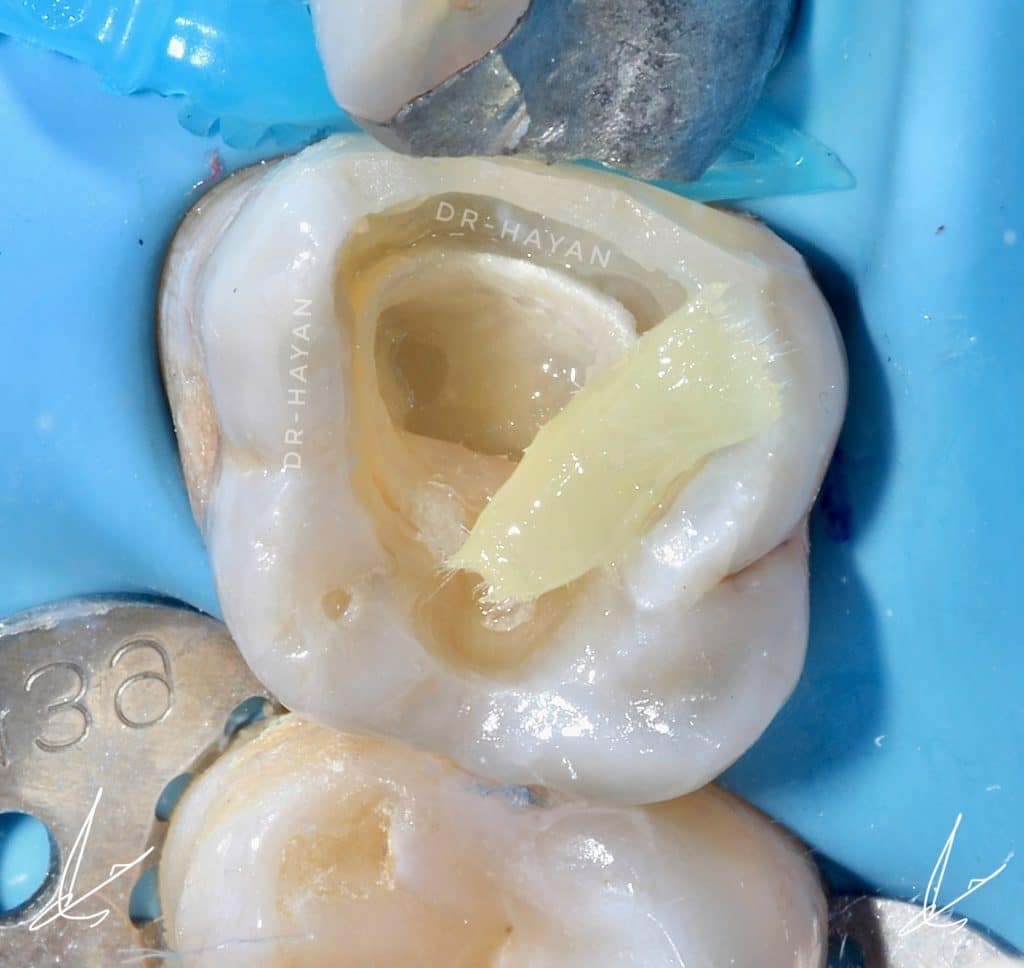

After total etching and application OT prime

For Deactivate matrix metalloproteinases. This prevents 25% to 30% of bond strength from being degraded.45 Deactivation can be achieved by using a 30 second treatment with ot prime or CHX

Then bonding and resin coating on dentine

Resin coat the immediate dentin sealing. This can be done with a flowable resin or a lower viscosity restorative composite with a modulus of elasticity of around 12 GPa. This ensures that the dentin bonding system is fully polymerized even if the pressure of pulpal fluid transudation (in conjunction with the air-inhibited layer) has made the adhesive too thin to be polymerized due to airinhibition. Once the dentin bonding system is resin coated and the resin coating is light polymerized, the air inhibition and transudation stop. This step also creates a “secure bond,” which means that if the onlay was ever dislodged from the resin coating, the resin coating would stay bonded to the sealed dentin , after that should be

Decouple with time. This protocol states that polymerization shrinkage stress to the developing dentin bond of the hybrid layer should be minimized for a certain period of time (ie 5 to 30 minutes) by keeping initial increments to a minimum thickness (ie less than 2mm).

After deep marginal acquisition ✅

Bonding ✅

Resin coating ✅

Decouple with time✅

ready for DME and class II

Polyethylene fibers reinforced with an ultra-high modulus of elasticity, Therefore, they have been widely used to increase the fracture strength of restorative and prosthetic materials in dental practice. In addition, a polyethylene fiber network can effectively modify the stress dynamics at the interface between the enamel, composite, and adhesive materials, and it provides effective force transfer

Polyethylene fibre Ribbond was adopted to cavities using a bonding agent and a flowable composite.

For large restorations, place fiber inserts on pulpal floor and/or axial walls to minimize stress on the developing bond strength of the hybrid layer. The fiber nets allow the composite on either side of the net to move in different directions via micro shifting of the woven fibers. The polymer network is still highly connected, but the polymerization shrinkage does not stress the hybrid laye

Short Polyethylene fiber in middle bulk

,Ever x flow and ever x packable in midel

Everx need to stop a little lower , leave around 1.5-2mm for the packable compsite

Bulk fill flow SDR to smoothing the restoration and fill the cavities

neospectra composite shade A3

Layering cups by cusp

Before finishing

The homogenization of marginal acquisition, DME and mesial wall bulding up

Most important step for hermetic contact